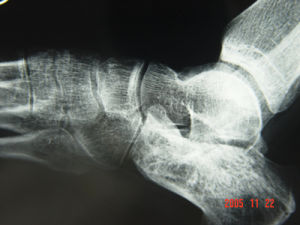

五、影像學檢查

關節疾患X線拍片是常規的檢查方法之一主要查看骨質的變化,特別是對關節部位骨腫瘤,骨質破壞畸形、關節滲液腫脹,有明顯的診斷意義CT及MRI也是檢查關節病變新的方法,除對骨質顯像之外,對關節內的軟骨軟組織結構能夠顯像丶,對診斷半月板損傷有其先進之處,這是普通X線拍片所不能比擬的其缺點是價格較昂貴。